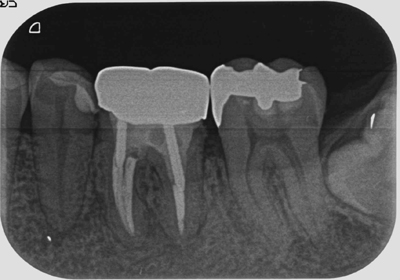

症例3【50代男性】左下第一大臼歯の根尖病巣。

根管内の殺菌・消毒を約3ヶ月間行うことにより、病巣はほぼ消失、硬線が明瞭に見える。

治療前

治療後(14ヶ月後)